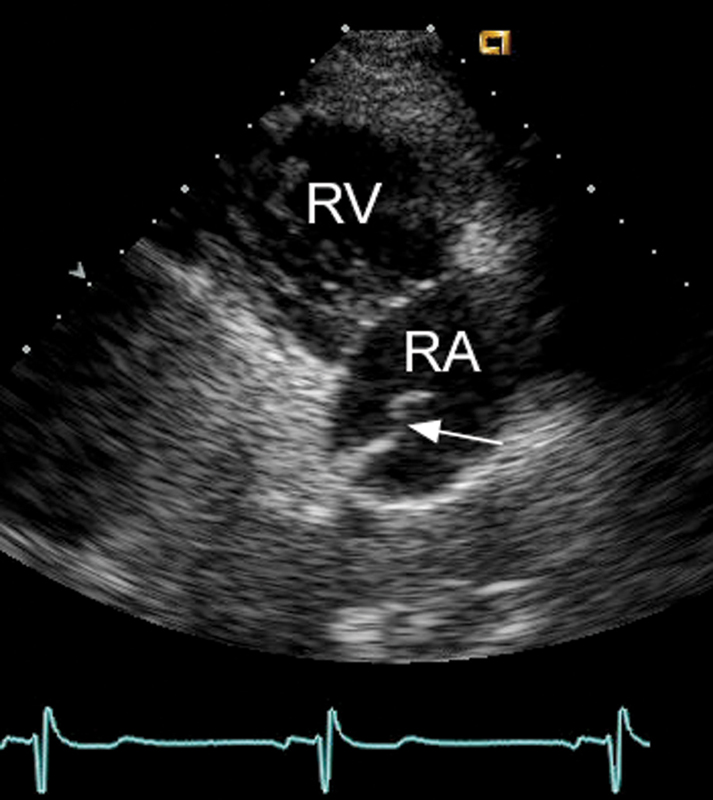

فحوصات تشخيصية لبعض امراض القلب والشرايين التاجية